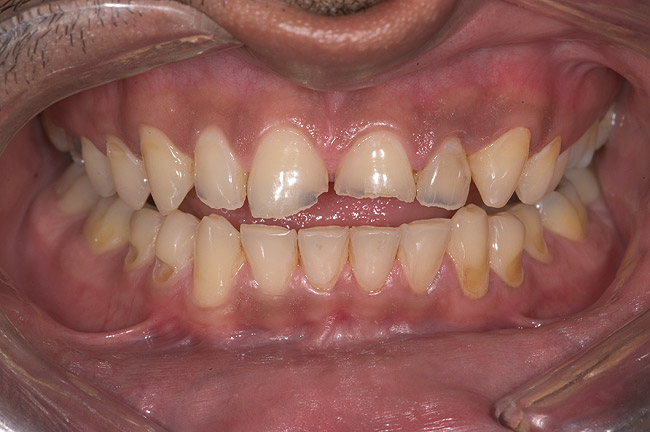

Figure 6  1:1 view demonstrating severe loss of tooth structure due to palatal erosion.

Figure 6

Examination revealed that palatal surfaces of teeth Nos. 6 through 11 showed severe loss of tooth structure, with mild wear on the lower incisors and loss of anterior guidance (Figure 5 through Figure 7). The palatal TSL was consistent with the clinical picture presented by patients with gastric reflux. A detailed medical history was taken, and the patient complained of having heartburn and acidity at least 4 out of 7 days a week. He had never sought treatment for it and used over-the-counter medication when needed. He was a nonsmoker, with occasional intake of alcohol. He had a high-stress job with irregular meal times. A thorough smile and dental analysis11 was carried out; the findings appear in Table 2.